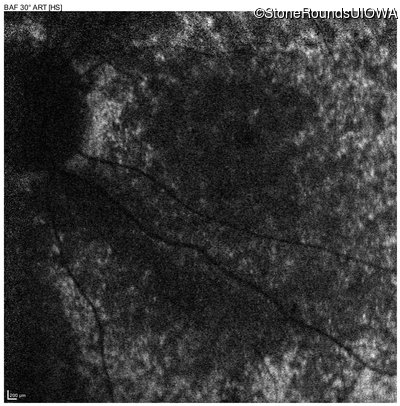

AR Stargardt Disease (IIA)

Age at visit: 8 years

This 8 year old girl had normal vision until age 6 when she failed a school vision screening. That year, she was able to play softball well, but this year she often loses sight of the ball and is often hit by it.

AR Stargardt Disease ABCA4 IVS38-10T>C IVS38-10T>C AR